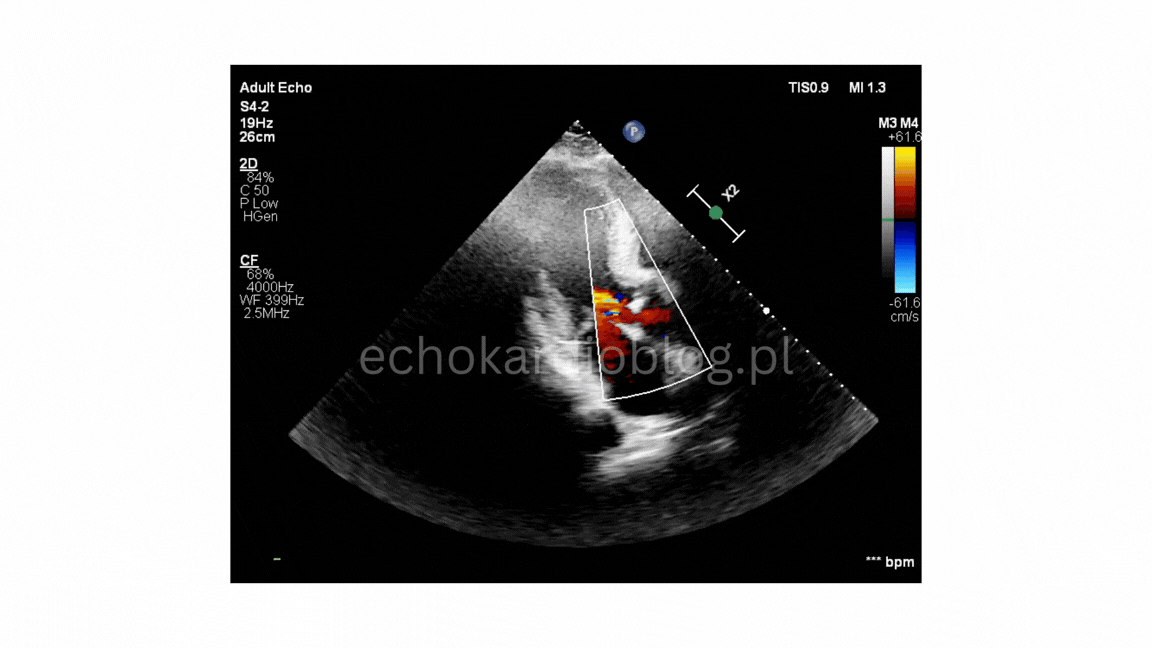

Przypadek 3.A

Przypadek 3.B

Przypadek 3.C

Przypadek 3.D